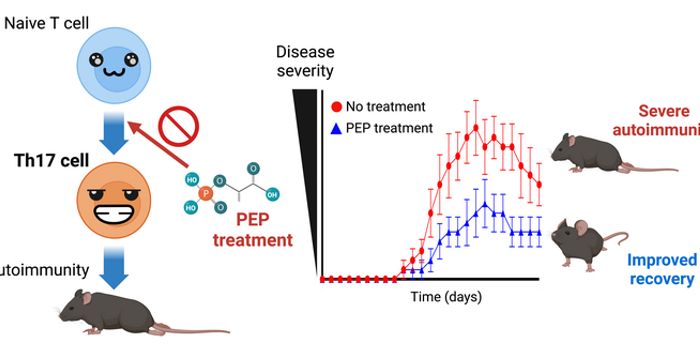

JUN 05, 2015ImmunologyIf you want your children to reap the benefits of a more responsive immune system, teach them about altruistic giving.JAN 30, 2018Health & MedicineThis flu season has been one of the worst in recent memory. While health professionals still recommend getting a flu vac ...AUG 18, 2020ImmunologyDolphins are helping scientists answer the age-old question: can we stop the clock when it comes to aging? A recent stud ...APR 11, 2023CancerMonoclonal antibodies have revolutionized cancer therapy since their introduction as therapeutics in the field. To enhan ...JAN 03, 2017ImmunologyA vaccine for cancer is on the horizon, although it works in a way different to what most people might consider a conven ...DEC 02, 2016CancerGood news for patients with early stage skin cancer: a combination drug seems to be effective at attacking the skin canc ...SEP 26, 2016ImmunologyA new drug candidate for multiple sclerosis (MS) was successfully tested in mice models of the disease. The drug, called ...JAN 11, 2021ImmunologyMacrophages are a type of immune cell that can detect and destruct bacteria, viruses, and harmful materials. They a ...NOV 19, 2020ImmunologyParasitic worms known as helminths have a complicated relationship with the immune systems of the hosts they invade. Ter ...DEC 15, 2015ImmunologyA specific group of antibodies are nurtured by the immune system to fight HIV. This process naturally occurs in the pres ...NOV 11, 2021ImmunologyGlobal vaccination efforts continue in the backdrop of the ongoing pandemic. However, new studies demonstrate how severa ...MAR 10, 2015ImmunologyScientists at Albert Einstein College of Medicine of Yeshiva University, Bronx, NY, have designed a new type of vaccine ...AUG 05, 2021TechnologyToday, the Ethernet connection has emerged as one of the most popular ways to make the most out of an internet connectio ...APR 09, 2015Genetics & GenomicsIn a first study to test a new generation of HIV antibodies in humans, an experimental therapy lowered the virus amount ...NOV 17, 2019Cell & Molecular BiologyWhen people get sick, they often also feel tired, which can be as troublesome as their disease.JAN 12, 2022Health & MedicineWith the pandemic coming up on its 2-year anniversary, the ironic question more people are contemplating with this less ...DEC 31, 2020ImmunologyBumpy, inflamed, ring-shaped lesions on the skin—granuloma annulare (GA) is a chronic, inflammatory skin condition ...NOV 25, 2022Drug Discovery & DevelopmentLong-term antibiotic use to treat adolescent acne disrupts the gut microbiome and impairs bone maturation. The correspon ...AUG 02, 2017ImmunologyThere is a connection between autophagy, a process that keeps a cell clean of trash and debris, and Crohn’s diseas ...FEB 02, 2023ImmunologyHistotripsy is a technique that uses sound waves to rip tumors apart, without even breaking the skin. The non-invasive w ...DEC 19, 2017ImmunologyThere’s more to blood platelets than blood clotting, according to scientists from Ludwig-Maximilians-Universitat M ...MAY 20, 2019MicrobiologyStress can have a detrimental effect on our health, and appears to contribute to the development of autoimmune diseases.NOV 09, 2020Drug Discovery & DevelopmentResearchers from Thomas Jefferson University in Philadelphia are studying an immunotherapy that has shown early pro ...MAR 06, 2018ImmunologyA new, non-antibiotic approach to targeting bacterial infections like Staphylococcus aureus - which are notoriously diff ...AUG 06, 2019MicrobiologyA standard research mouse genotype was preserved while generating a natural microbiome by using wild mice as surrogates.NOV 03, 2014ImmunologyThe news is frightening, whether you live in or travel to places where you might be likely to be exposed to it or whethe ...AUG 20, 2014NeuroscienceOnly about 1% of Americans have schizophrenia, but the agitation, hearing of voices, and paranoia it causes can lead to ...OCT 19, 2016Chemistry & PhysicsCrystallography Solves Unknown Structure of Novel Mosquito Toxin That Can Help Control ZikaNOV 05, 2018ImmunologyScientists at Vanderbilt show that the amino acid glutamine can contribute to a subset of T cell function and activationJUL 19, 2018MicrobiologyFor many years, scientists have been trying to learn more about the causes of autism.JUL 27, 2021ImmunologyA study by immunologists at the University of Copenhagen has revealed a never-before-seen immune pathway invol ...JUL 18, 2016Immunology"This study makes it clear that resveratrol does cause the immune systems of dogs to change, but the changes it cau ...AUG 18, 2021Cannabis SciencesPeople with a genetic predisposition to cannabis use disorder (CUD) are more likely to require hospitalization after con ...MAR 31, 2021MicrobiologyScientists took an exploratory journey to a place in the central Pacific Ocean in Kirbati called the Phoenix Islands Pro ...DEC 14, 2023CancerAnixa Biosciences, a publicly traded (Nasdaq: ANIX) biotechnology company based in San Jose, California, recently announ ...FEB 21, 2020Drug Discovery & DevelopmentUsing AI, researchers at MIT have found a powerful new antibiotic capable of killing some of the most dangerous drug-res ...APR 05, 2016CardiologyMany people applaud red wine for its health benefits, however vague these benefits are often presented. A new study from ...AUG 23, 2021CancerImmunotherapies are emerging as a promising strategy for the treatment of late-stage cancers which currently have m ...MAR 09, 2021ImmunologyResearchers have developed a CRISPR treatment that could potentially treat both viruses that cause COVID-19 and influenz ...JUL 19, 2016MicrobiologyThe common cold virus grows best at cooler temperatures (like in your nose), just a few degrees below core body temperat ...OCT 20, 2022CancerThe gut microbiome describes the microorganisms and viruses that live throughout the digestive system. The gut mic ...FEB 07, 2021MicrobiologyAfter years of effort, researchers are reporting that there were encouraging results from a phase 1 clinical trial which ...MAR 29, 2016ImmunologyIf a child with a food allergy has a life-threatening reaction, parents need to know how to act, but many say doctors ar ...AUG 31, 2021ImmunologyAfter encountering an infectious agent, the immune system begins churning out antibodies—Y-shaped warriors that ne ...APR 17, 2014Cell & Molecular BiologyWe all had Silly Putty as children, the wonderful toy that we used for everything from bouncy balls to pencil holders to ...MAR 04, 2016ImmunologyAll food allergies are not created equal. In fact, researchers from the University of Southampton set out to prove just ...APR 16, 2020Health & MedicineAs mortality and infection rates rise globally, it appears that SARS-CoV-2, the virus responsible for the COVID-19 pande ...MAR 04, 2015ImmunologyRats in New York City carry a species of flea that is capable of transmitting plague pathogens.